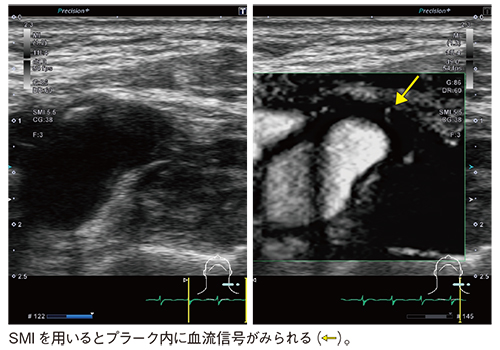

図3 症例2:脳梗塞精査にてPLI-705BXにより治療が変更となった症例

SMIは,全身のさまざまな領域に用いられており,造影剤を使用することなくプラーク内新生血管内の微細な血流評価も可能である(図4)。これは,SMIが低流速な血流の評価に有用であることを示していると言える。